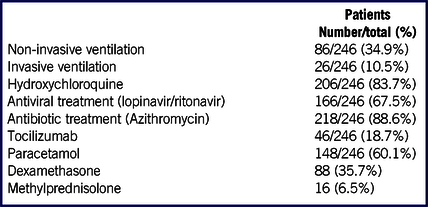

Most of the patients received a combination of antibiotics and antiviral therapy (152/246 patients; 62%). Patients’ treatments are listed in Table 3.

TABLE 3 Patients Treatment During Hospitalization

In our case series, most of the patients were treated with hydroxychloroquine, an analog of chloroquine with a better safety profile, and fewer drug interactions, that showed in vitro antiviral activity against SARS-CoV-2.Reference Liu, Cao and Xu31 As the epicenter of COVID-19 shifted from China to Europe, the use of hydroxychloroquine was recommended also by European authors as a possible prophylaxis and curative treatment for COVID-19Reference Colson, Rolain and Raoult32,Reference Colson, Rolain and Lagier33 ; therefore, we adopted its use in our COVID-19 treatments. The effective benefits form this treatment still remain unclear,Reference Funck-Brentano and Salem34 and its use is now limited to clinical studies.35